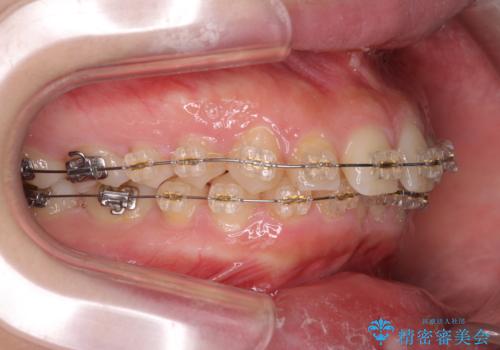

深い噛み合わせ、すきっ歯の改善 ワイヤーを用いたマルチブラケット矯正

- 噛み合わせが深く、前歯が突き出て隙間が出てきたことの改善を希望され矯正治療の相談で当院に初診来院されました。

ワイヤーを用いたマルチブラケット矯正を行うことで深い噛み合わせを改善し、前歯の隙間もなくし審美的な歯列へと治療をおこなっていきます。

深い噛み合わせの改善は前歯の圧下が必要なため、治療期間が長期化することが多いです。